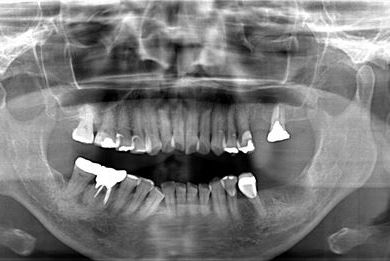

インプラントの症例写真 IMPLANT

インプラント治療+ソケットリフト+GBR

| 性別/年齢 | 女性 / 55歳 | ||||||||||||||||||||||||||||||||

| 主訴 | 奥歯が3本抜歯されてしまったあとにインプラントを入れたい。 | ||||||||||||||||||||||||||||||||

| 治療内容 | インプラント3本(ソケットリフト、GBR)、ハイブリッドセラミック3本 | ||||||||||||||||||||||||||||||||

| 総治療費 | 1,295,300円 | ||||||||||||||||||||||||||||||||

| 治療期間 | 8ヶ月 |